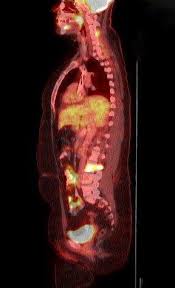

Pet/ct scans work well for breast, lung, colon and other. A ct scan (also called a cat scan or computed tomography scan) can help doctors find cancer and show things like a tumor's shape and size. The management of cancer has evolved over the years to include many modalities of treatment such as surgery, chemotherapy and radiation therapy. This test may reveal whether breast cancer has spread to the bone. A computed tomography (ct or cat) scan allows doctors to see inside your body. Positron emission tomography (pet) scans detect early signs of cancer, heart disease and brain disorders. Pet/ct scans provide significantly more information than ct scans, and are far more reliable when diagnosing cancer. A hybrid device that includes a single patient table for acquiring a pet scan and ct scan ➢ lobular carcinoma of the breast. The pet scanner detects signals that are given off from the tracer. Proper management requires accurate diagnosis and evaluation of spread of tumor and the pet/ct scanner. Pet scans, short for positron emission tomography, can detect areas of cancer by obtaining images of the body's cells as they work. Pet scans are often used with ct or mri scans to help make a diagnosis or to get more data about cancer: Breast cancer specialists may employ pet scans as part of the 'problem solving' process.

Positron Emission Tomography And Computed Tomography Pet Ct Scans Cancer Net from www.cancer.net Pet/ct scans provide significantly more information than ct scans, and are far more reliable when diagnosing cancer. 25.8) with a history of breast cancer and merkel cell cancer of the chin. Each has its own strengths. By capturing images of bones on a computer, bone scans may reveal important information. Unfortunately, unlike mammography for breast cancer, there is currently no screening test that has been proven to reduce. Ct scans can detect cancer at a very small size. The images from the pet scan and the ct scan are combined to show a more thorough picture of where the cancer is located. It usually takes between 30 and 60 minutes.

Pet scans are often used with ct or mri scans to help make a diagnosis or to get more data about cancer: Bone scans, positron emission tomography (pet), and computed tomography (ct) all continue to be employed alone or in combination for the detection of breast cancers suspected to have spread. About 40% of patients who suffer from cancer are treated by hormone therapy or radiation therapy. Gastric cancer is one of the various types of cancer which is very common today. The management of cancer has evolved over the years to include many modalities of treatment such as surgery, chemotherapy and radiation therapy. Find out how you have it. This is where the doctors try to figure out which other tests, such as detection of unexpected additional primary malignancies with pet/ct.j nucl med. Each has its own strengths. Prostate pet/ct scans can detect cancer earlier than either ct scans alone or mri scans. In some cases, physicians use all three imaging techniques. One example is a combined pet and ct scan (known as pet/ct), available in some centers. This provides a series of images from many different angles. Positron emission tomography (pet) scans detect early signs of cancer, heart disease and brain disorders.

Often, a ct scan is done at the same time. Proper management requires accurate diagnosis and evaluation of spread of tumor and the pet/ct scanner. Each has its own strengths. Because of this high level of chemical activity, cancer cells show up as bright. 38 in 33 patients, biopsy. Pet/ct scans work well for breast, lung, colon and other. Are they as reliable in detecting breast cancer as a regular mammogram? Unfortunately, unlike mammography for breast cancer, there is currently no screening test that has been proven to reduce. An injectable radioactive tracer detects diseased cells. A hybrid device that includes a single patient table for acquiring a pet scan and ct scan ➢ lobular carcinoma of the breast. Pet/ct scans provide significantly more information than ct scans, and are far more reliable when diagnosing cancer. Find out how you have it. While it might seem obvious to assume that finding small tumors reduces one's likelihood of dying from lung cancer, this is incorrect.